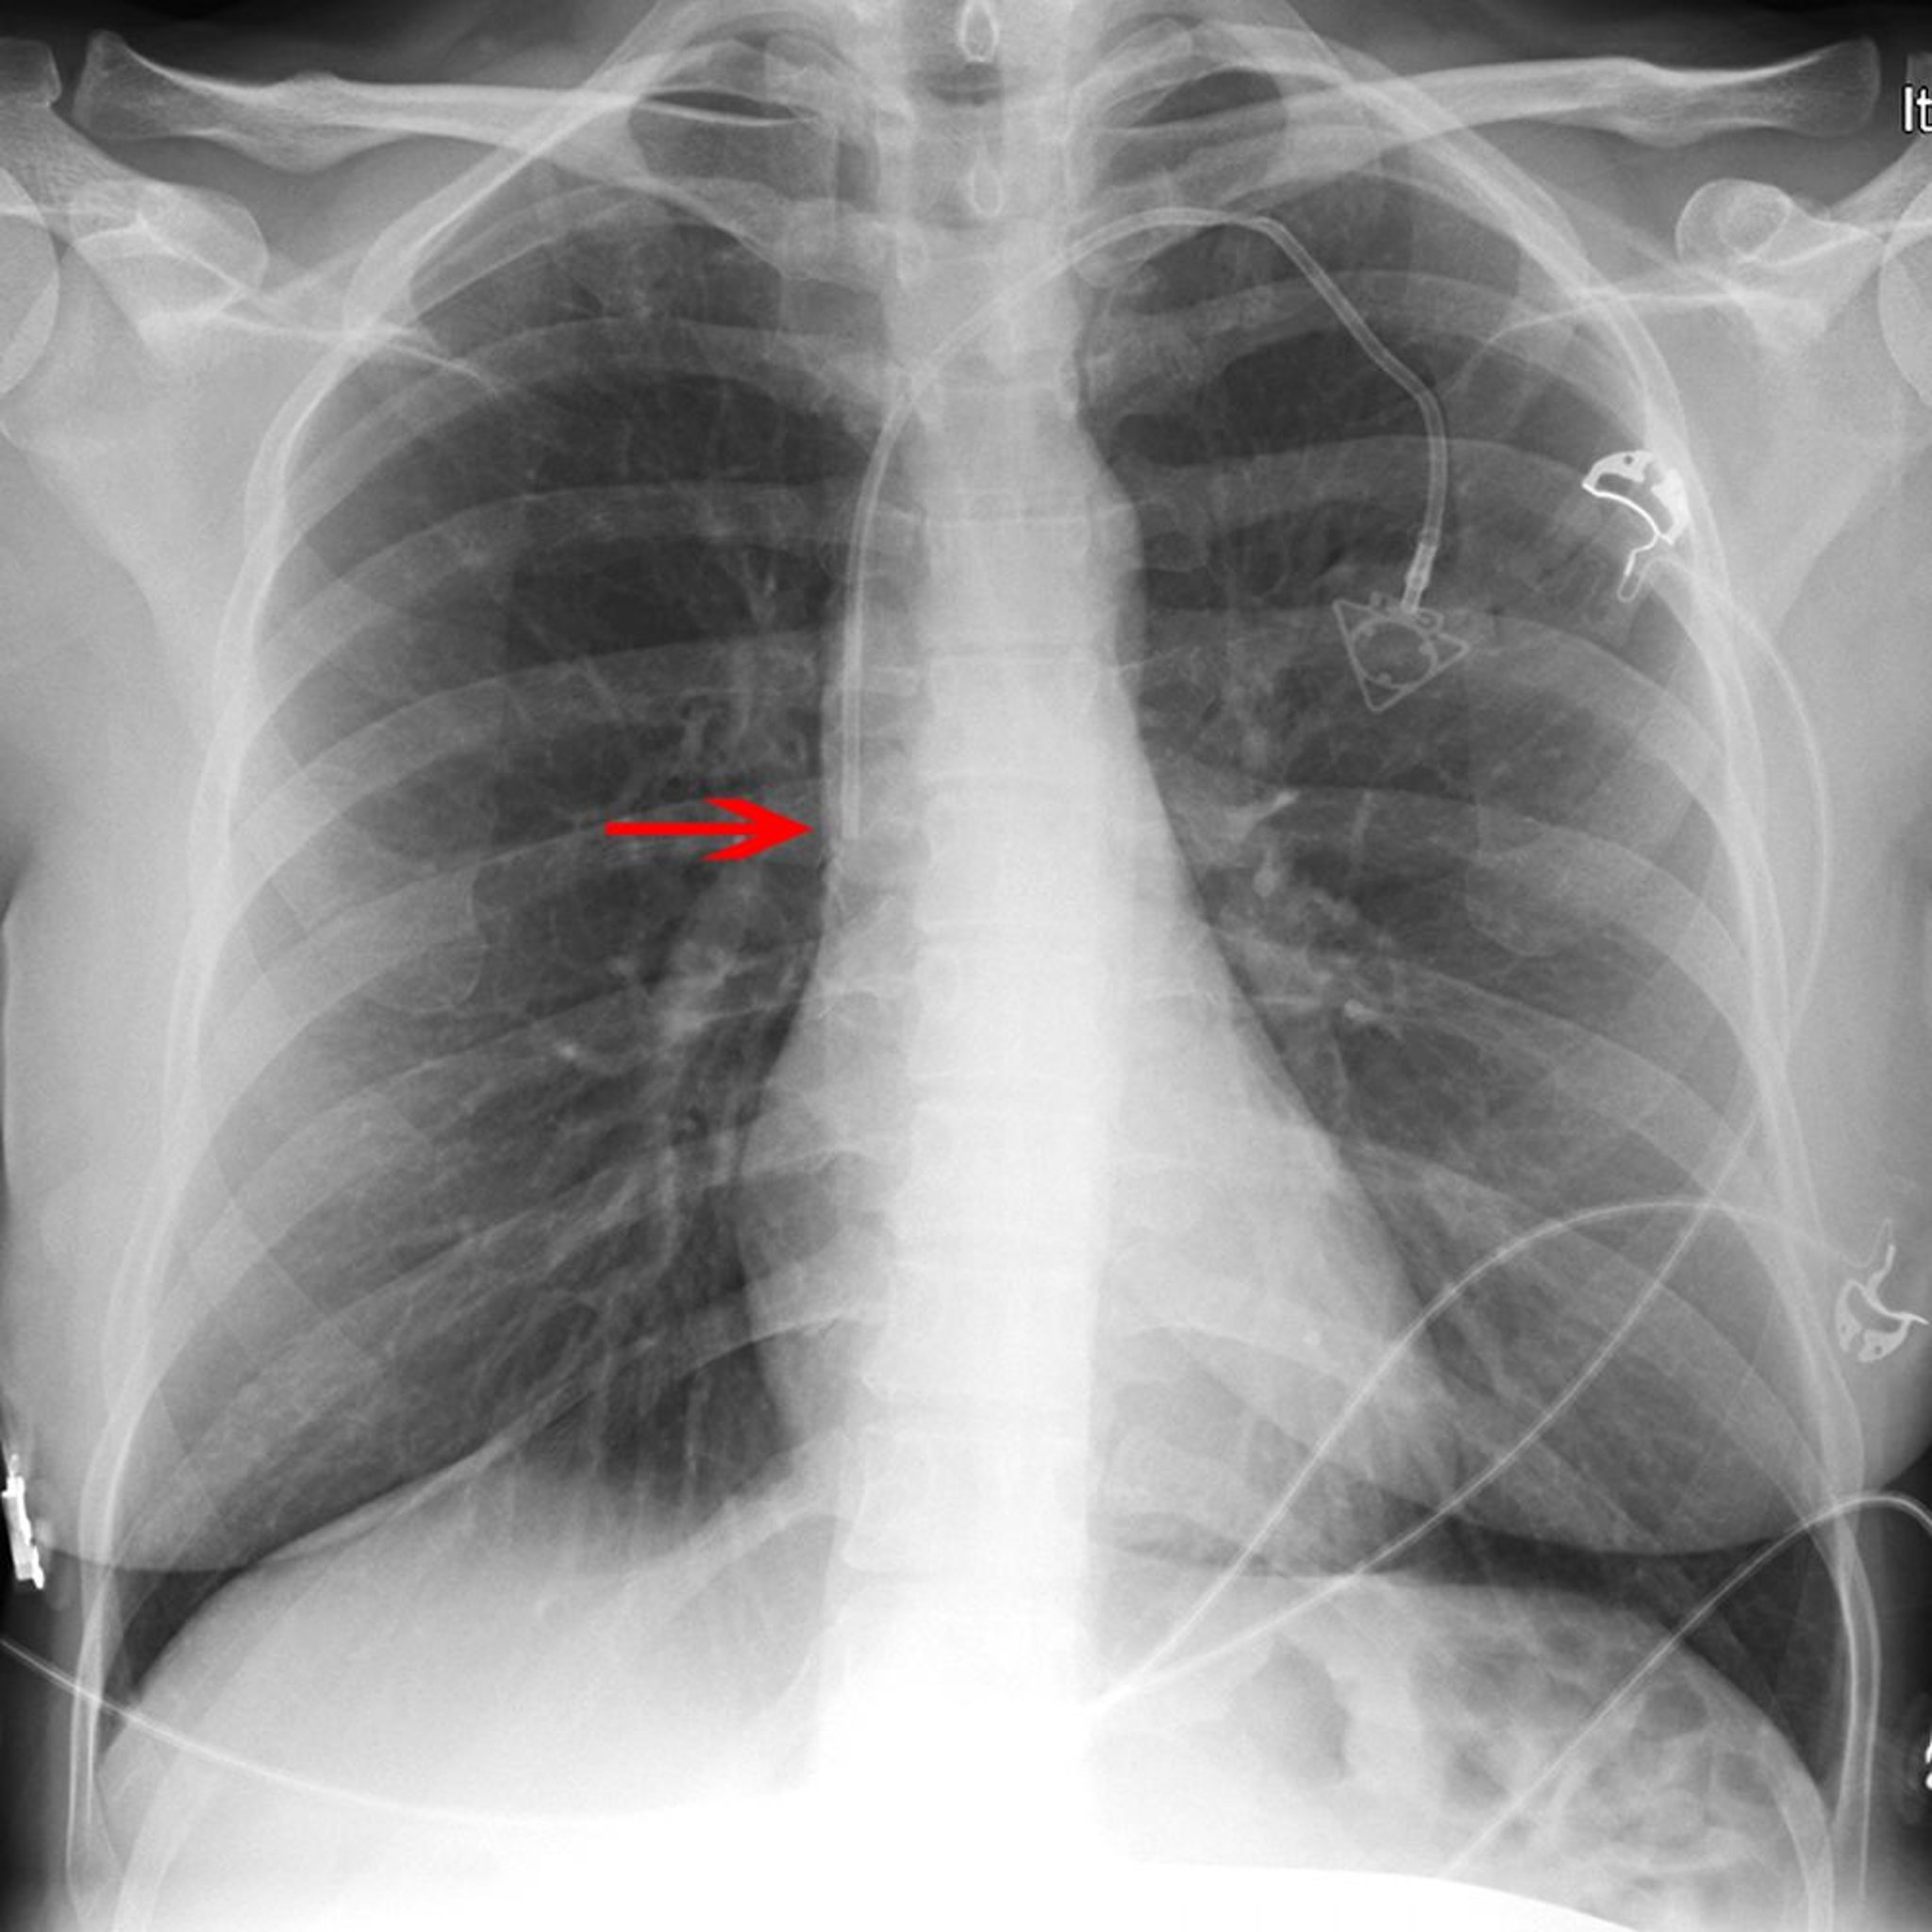

Рентгеновский снимок центрального венозного катетера

Красная стрелка указывает на кончик левого подключичного катетера (размещен соответствующим образом в нижней части верхней полой вены).